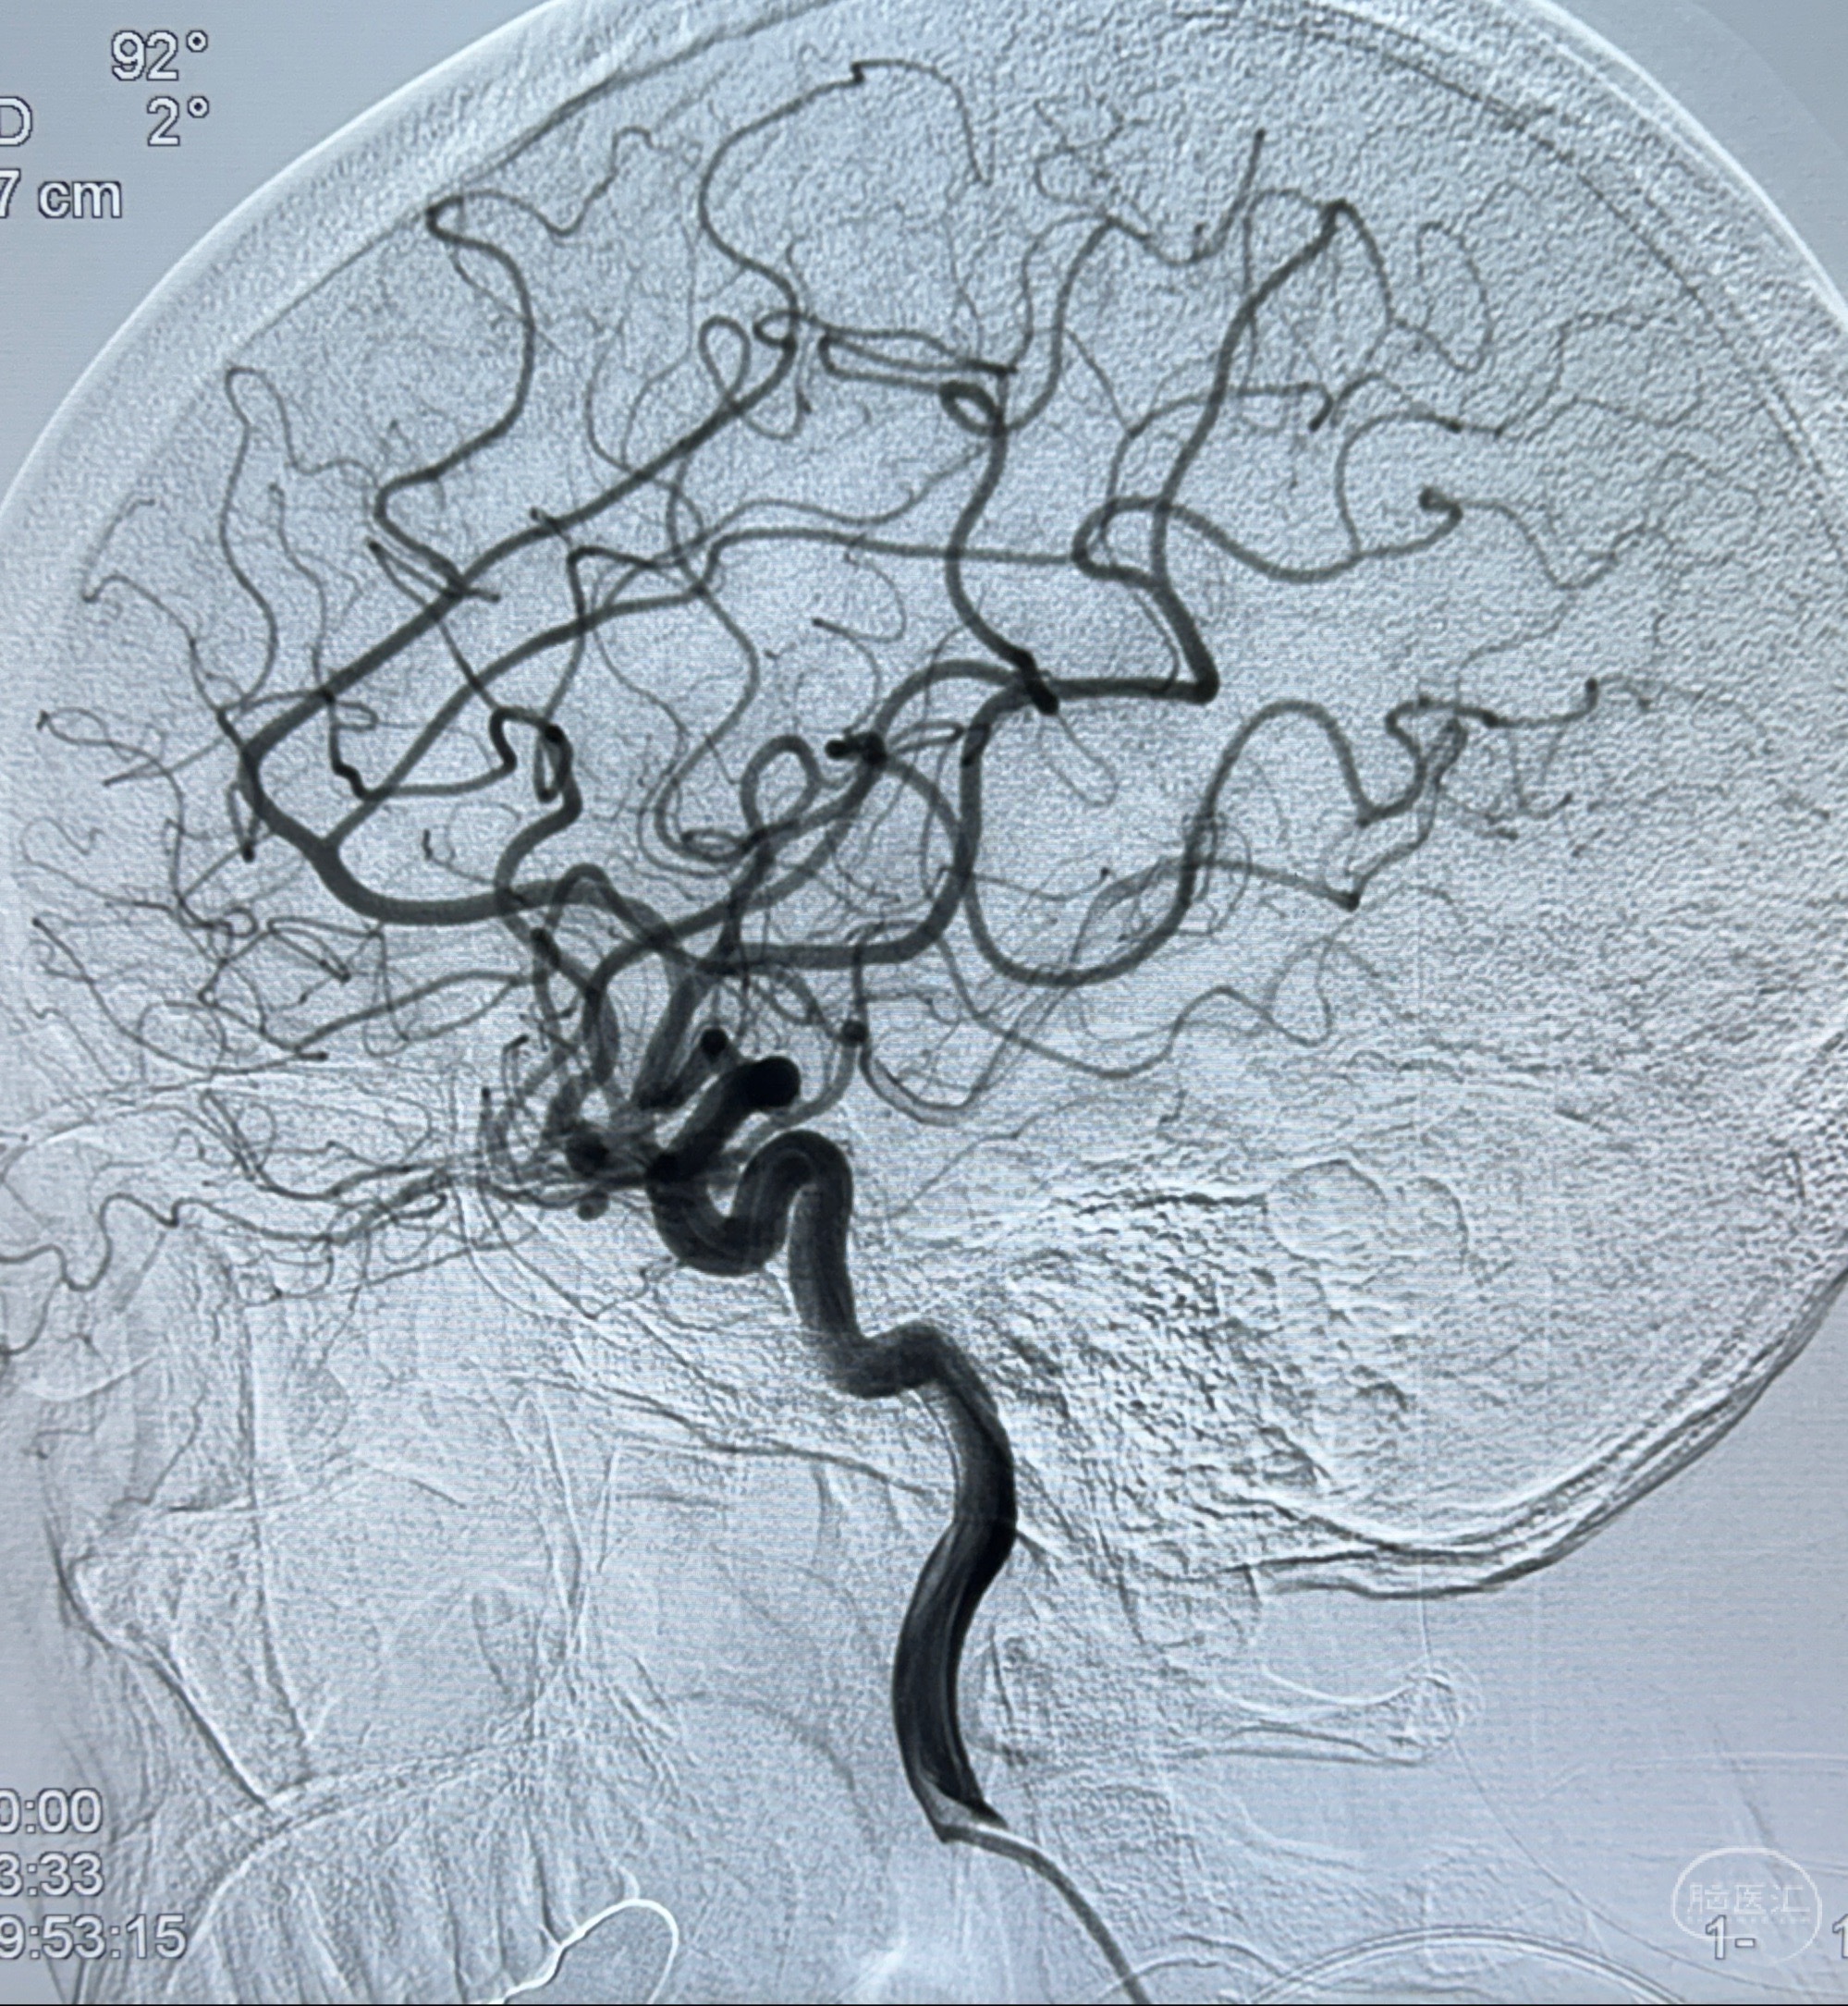

2023-11-24DSA:右侧大脑中动脉下干起始部动脉瘤,约2.3*2.5mm,形态规则

2023-12-04全麻下行支架辅助治疗

S-AB4-20mm